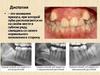

Степень аномального положения зуба (дистопии) может быть

различной от небольшого отклонения продольной оси по

отношению к норме до расположения зуба в верхней половине

ветви нижней челюсти